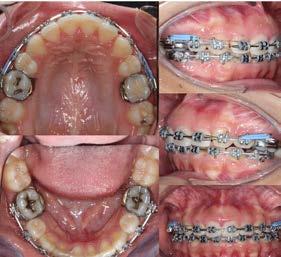

Estudio comparativo, observacional y experimental in vivo. Se empleó en una paciente femenina de 56 años de edad; valorada en la clínica de rehabilitación oral del Centro de Estudios Multidisciplinario de Rehabilitación Oral, (CEMRO), en Tarímbaro, Michoacán; quién decidió hacer un cambio en su sonrisa debido a que esta le generaba insatisfacción, cambiando sus restauraciones antiguas, deficientes en el sector anterior; para lo cual se planeó el retiro de 5 coronas de metal-porcelana de los OD 11,12, 13, 21 y 22 vitales, las cuales serán confeccionadas mediante técnica CAD/CAM realizando su historia clínica y autorizando su consentimiento informado.

Se planteó la utilización de cerámica feldespática e-max de la casa comercial Ivoclar Vivadent, en la presentación de bloques para la realización de las coronas totales en los OD

11, 12 y 13 mediante técnica CAD/ CAM, en su versión HT, color A2. Por otro lado, las otras 2 coronas de los OD 21 y 22 fueron confeccionadas con disco de zirconia Zahndent en tono A2. Estas fueron puestas a prueba mediante la aplicación Adobe Photoshop, con ayuda de una fotografía de las coronas tomada antes de su cementación definitiva, y una segunda medición con las coronas ya cementadas, únicamente se realizó el análisis en los OD 11 Y 21, los cuales fueron cementados con cemento translucido Multilink Speed de Ivoclar Vivadent, se tomaron fotografías con cámara profesional Cannon T8 y lente macro 100mm. Es importante mencionar que decidí utilizar cemento dual translucido para evitar alteración en el color de las coronas ya cementadas, con el fin de obtener mediciones puntuales de color y determinar las cantidades de pigmento que hay en cada corona mediante un fondo negro y así poder corroborar que se logró un buen mimetismo. El tiempo estimado para el procedimiento fue de 5 citas.

La medición se llevó a cabo por medio de la aplicación Adobe Photoshop, señalando 3 puntos en cada corona del tercio medio hacia incisal. Por cada punto, Adobe Photoshop trabaja con base en un sistema aditivo de color (RGB), que trabaja en una gradación de color desde el 0 hasta el 255, por lo que hay 256 gradaciones de color por canal. Una vez obtenidos los colores, fue necesario trasladar los resultados a un

Figura 1. Coronas antes de su cementación (Francisco Javier Méndez Landa 2024).

porcentaje de 0 a 100, obteniendo el porcentaje exacto de cada uno de esos colores, que una vez mezclados obtenemos el tono real de las coronas (Figura 1).

Se realizó la medición del color de las coronas mediante una fotografía en formato RAW en fondo negro (Figura 2).

Se muestra un análisis del proceso de medición de color de las coronas antes de su cementación y cómo se obtuvieron los resultados, mediante la aplicación Adobe Photoshop (Figura 3).

Se muestra una fotografía del análisis de los incisivos centrales, los cuales fueron confeccionados: el órgano

Figura 2. Proceso del análisis del color en Adobe Photoshop (Francisco Javier Méndez Landa 2024).

dentario 11 con disilicato de litio y el órgano dentario 21 con zirconio.

Resultados

Los resultados obtenidos fueron que, en promedio, sí existe variación de los pigmentos en cuanto a la medición de la mezcla de los 3 colores antes de ser cementadas las coronas del canino, incisivo central y lateral superior derechos; las cuales fueron confeccionadas con e-max, en una escala de 0 a 255 que arroja la aplicación Adobe Photoshop obteniendo los siguientes valores: en cuanto al canino superior derecho, se obtuvieron valores del color rojo: 195, del color verde: 179 y del color azul: 157. Del incisivo lateral izquierdo superior se obtuvo del color rojo: 197, del color verde: 181 y del color azul 161. Del incisivo central superior izquierdo se obtuvo del color rojo: 195, del color verde: 180 y del color azul: 158. En

cuanto las otras 2 coronas restantes, las cuales fueron confeccionadas con zirconio del incisivo central superior derecho obtuvimos del color rojo: en promedio 196, del color verde: 181 y del color azul: 161. Del incisivo lateral superior derecho del color rojo obtuvimos: 187, del color verde: 174 y del color azul: 156.

Se realizó un segundo análisis con las coronas ya cementadas en boca, únicamente de los incisivos centrales superiores, ya que uno fue confeccionado con disilicato de litio y el otro con zirconio. En este caso obtuvimos como resultado en la corona de disilicato de litio: del color rojo: 172, del color verde: 148 y en cuanto al color azul: 123. En la corona de zirconio obtuvimos del color rojo: 171, del color verde: 143, y del color azul: 119; en la escala de 0 a 255 que arroja la aplicación de Adobe Photoshop.

Podemos afirmar que también hubo variación y a pesar de utilizar 2 tipos de cerámicas diferentes, se logró obtener un buen mimetismo, dando como resultado un resultado satisfactorio para la paciente.